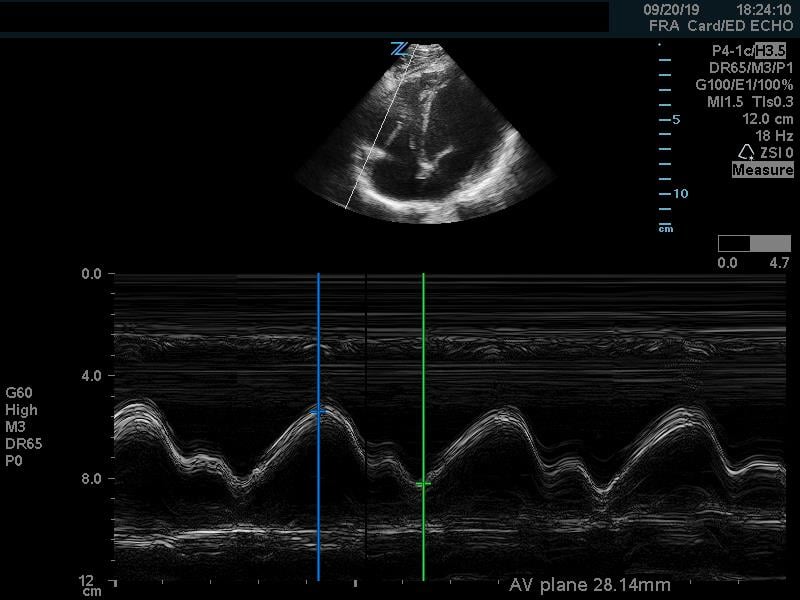

In addition to comparison of chamber size, one can further quantify RV function by using Tricuspid Annular Plane Systolic Excursion (TAPSE). This measurement indicates RV systolic function. In the apical 4 chamber view, place an M mode line through the lateral aspect of the tricuspid annulus. Measure the distance the annulus travels during the ventricular cycle. A normal TAPSE is generally 20mm or greater. (Video 5) (Figure 10) A TAPSE less than 16mm is concerning for RV strain. (Figure 11)

Figure 10. Apical 4 chamber view. M-Mode measurement of TAPSE measuring 28mm, indicating normal RV systolic function